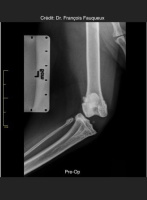

Radiologické snímky